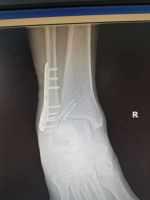

一例踝關節(jié)骨折的治療 關鍵疾?。?a href="http://m.akellydesign.com/tags/so/右踝關節(jié)骨折(旋后外旋2度)-4-1.html" target="_blank">右踝關節(jié)骨折(旋后外旋2度) 現(xiàn)病史【一般資料】 女性,69歲,離退休人員 【主訴】 右踝扭傷后腫痛活動受限2小時 【現(xiàn)病史】患者于2小時前在家中扭傷右踝部,致腫脹疼痛 不敢下地行走,當時無頭痛頭暈,無惡心嘔吐,急***就診,門診經(jīng)拍片檢查后以“右踝關節(jié)骨折”收入我病區(qū),患者自發(fā)病以來未進飲食,無發(fā)熱,右踝疼痛劇烈。 【既往史】既往體健,否認高血壓病、糖尿病、冠心病等病史;否認肝炎、結核等傳染病史;否認手術史和輸血史,否認食物、藥物過敏史,預防接種史不詳。 【個人史】生于原籍,無外地久居史,無煙酒嗜好,23歲結婚,月經(jīng)正常,無...

張*** | 副主任醫(yī)師 外科 骨科 瀏覽:3838